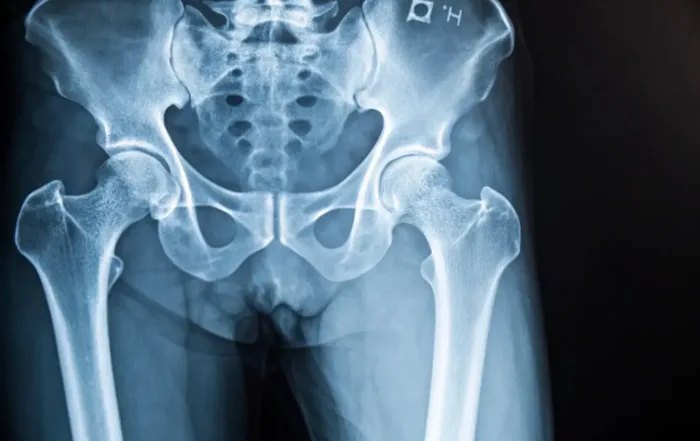

Medizinrecht: 30.000 Euro Schmerzensgeld für gebrochene Beine

30.000 Euro Schmerzensgeld für gebrochene Beine. Medizinrecht: 30.000 Euro Schmerzensgeld für gebrochene Beine wegen Fehler des Physiotherapeuten. Wie konnte es zu einem doppelten Beinbruch überhaupt kommen? Diese Frage klären wir auf und [...]